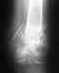

Re: Несрастающийся чрезвертельный перелом

Спасибо, что ответили. Проявлений инфекций нет. Предыдущие снимки пералага. Оперировалась первый раз в Обнинске, где произожло ДТП. Две последнии на платной основе в СПб, в ВМА.Сейчас нахожусь в кокситной повязке. На прошлой неделе обратились во Вредена. Рекомендации: принимать препараты кальция, снизить нагрузку на больную ногу. И все!